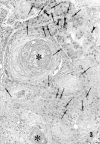

Methods: In Okinawa between 1986 and 1998, 1109 surgically resected lung tumours were examined histopathologically. In addition, human papillomavirus infection was detected by the polymerase chain reaction and Southern blot analysis in SCC cases reported in 1993 and 1995-8. Non-isotopic in situ hybridisation of HPV DNA was also carried out.

Results: Up until 1994 SCC, especially the well differentiated form, was the most prevalent type of tumour. However, since 1995 the number of such cases has diminished steadily, accompanied by a slight rise in the incidence of adenocarcinoma. Although most present and past patients are heavy smokers, the incidence of SCC, especially the well differentiated form, continues to decrease steadily. Furthermore, in 1993, HPV was detected in 79% of all cases, and was particularly prevalent in the well differentiated form, but the rate fell to 68% in 1995, 35% in 1996, 23% in 1997, and 24% in 1998. The age distribution of patients, the male to female ratio, and the number of tumours overexpressing p53 protein did not change significantly over the study period, and thus did not correlate with changes in the differentiation of SCC.